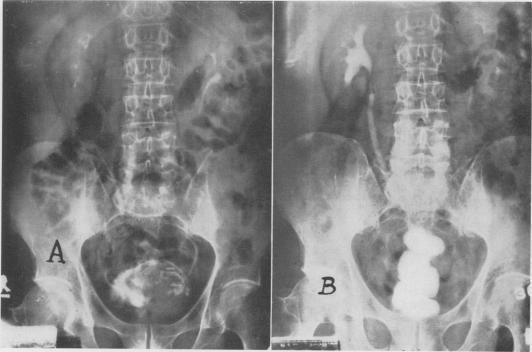

Ureterosigmoidostomy; experience with the Goodwin procedure.

Ann Surg. 1956 Mar;143(3):337-48. doi: 10.1097/00000658-195603000-00006.